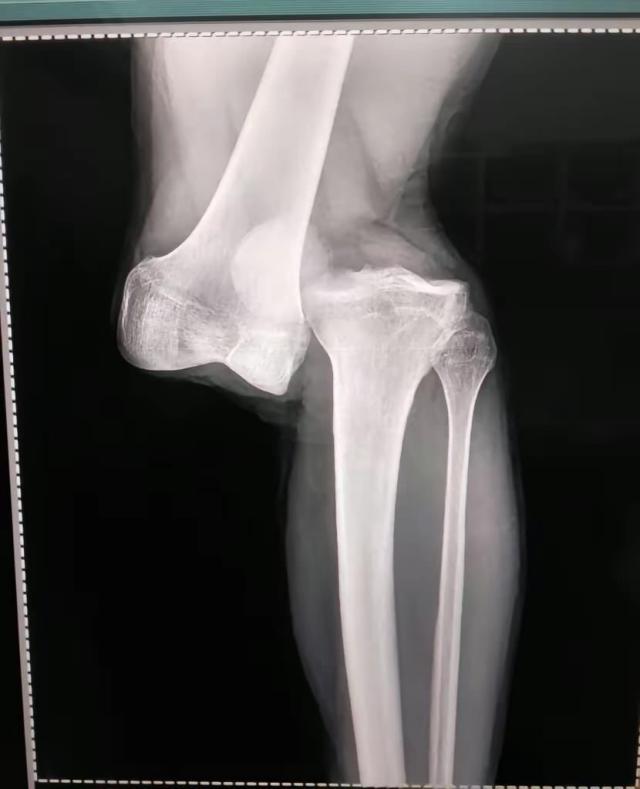

8月2日,做过检查,住院观察一夜之后,卢西亚诺·桑切斯坐着轮椅出了院。他的左膝脱了臼,大腿骨和腓骨分开了,三周之内做手术,可能一次手术还不行,得做多次手术,至少需要休息10个月,甚至有可能是1年。

8月2日接受阿根廷一电台采访,阿根廷青年人俱乐部队医亚历杭德罗·隆科罗尼说:“做了23年医生,我从没见过这么严重的伤病。(阿根廷队队医比利尼)干了40年医生,他对我说他也没见过一样的伤病。是膝盖完全脱臼。大腿骨和腓骨基本上分离了。前后十字韧带都撕裂了,我们还得看半月板情况怎样。”

谈及自己的伤情,卢西亚诺·桑切斯说:“我还好。刚开始时,是非常疼痛的时刻。由于运气,医生们第一时间成功地矫正了我的膝盖,这让我放松了很多。夜里我过得好,膝盖被固定住了,不疼。现在,我先回家,等待消肿,然后再决定什么时候做手术。”

下面是卢西亚诺·桑切斯受伤瞬间照片、在医院病床上拍的腿部照片以及X光检查结果,画面比较强烈,请谨慎考虑是否观看:

X光片